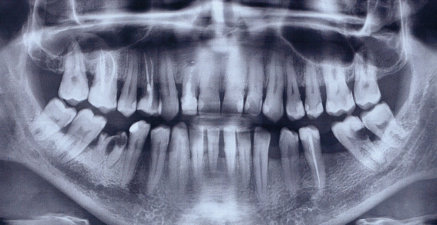

Добрый день. Особых проблем я не вижу, уважаемый пациент. 4.7 зуб необходимо тщательно осмотреть на предмет пригодных тканей для последующего восстановления вкладкой и коронкой, на 4.6 также есть воспаление на верхушке корня, все также необходимо пролечить затем изготовить культевую вкладку и коронку, 3.6 необходимо перелечить, плохая некачественная пломбировка, а также большая по площади пломба, при неблагоприятном исходе может привести к сколу стенки, что в последствии также к потере зуба, 2.6 скорее всего удалится, но еще раз стоит сделать ревизию, 1.6 необходимо перелечить.